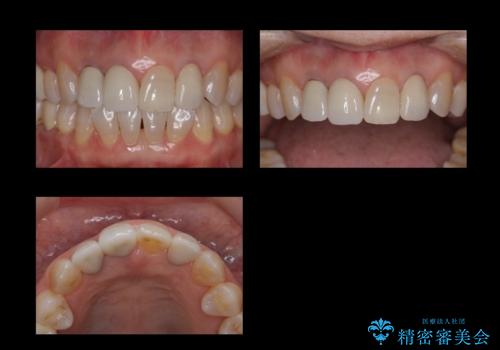

- 前歯のかぶせ物の際が黒いことを気にされて来院。

左上のかぶせ物になっていない歯は根の先に膿がたまっていたので根の治療をし、プラスチックでつぎはぎになっていたためセラミッククラウンでかぶせました。

- 61.6万円 内訳:右上12および左上2(ジルコニアクラウン14万円×3 仮歯1万円×3) 左上2(再根管治療 9万円、ファイバーコア2万円) 費用は治療当時の料金となります

右上12の二本の根の治療は特に行っておらずクラウンのみやり替えを行いました。